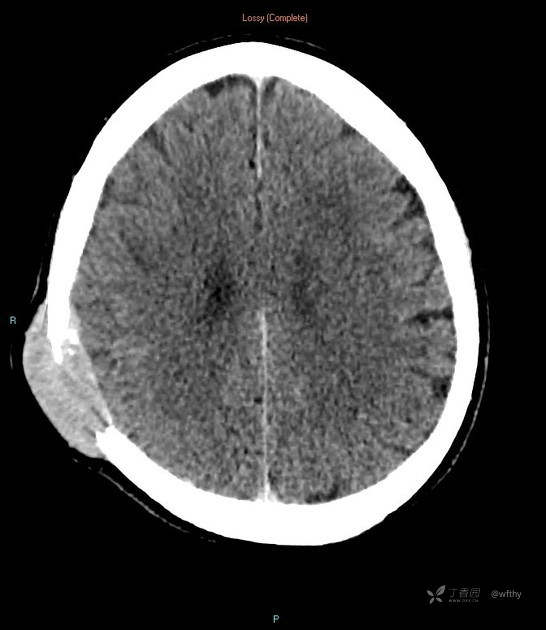

病例女65,头部肿块